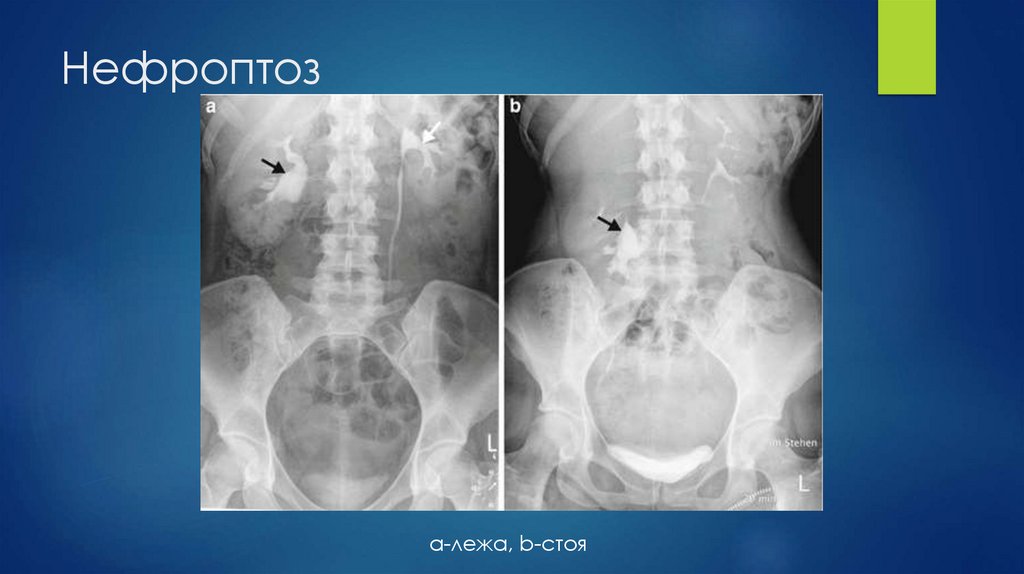

45. Нефроптоз

a-лежа, b-стоя